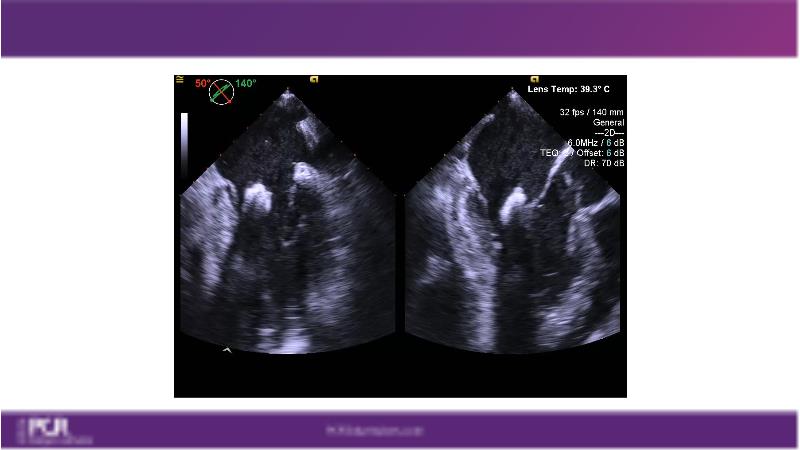

Watch this session to get an overview of a new TEER device, follow the step-by-step procedure related to initial experiences with this device for a Japanese patient with degenerative mitral regurgitation, learn about the latest data from RCT and registries, and follow discussions of challenging TEER cases!